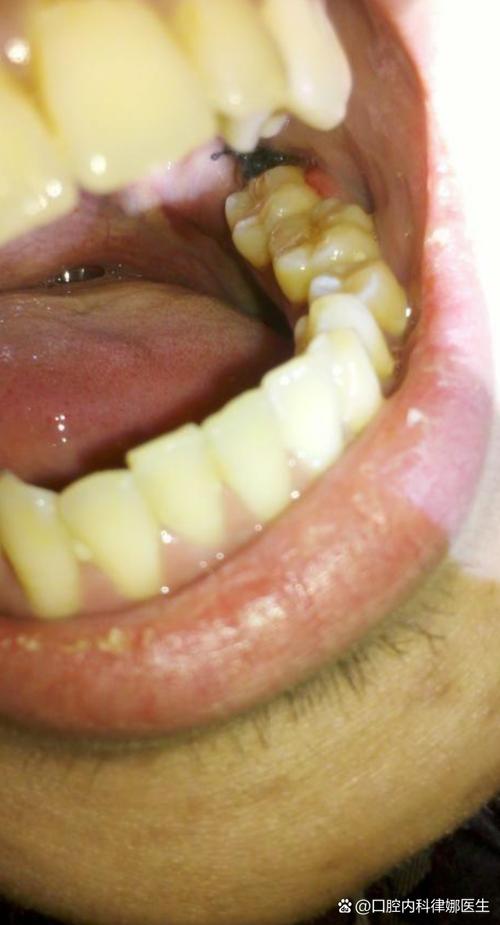

拔牙后洞里有食物残渣

(图片来源网络,侵删)